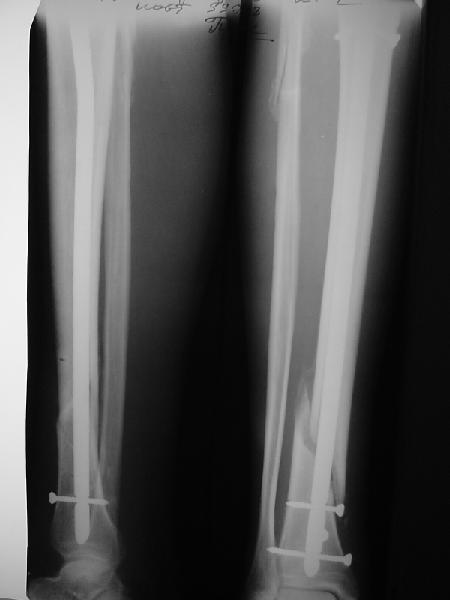

На мой взгляд, на снимках, приведённых Вами - неправильно сростающийся перелом дистальной трети большеберцовой кости, состояние после остеосинтеза интрамедуллярным гвоздём.

Как Вы пишите снимок под номером 1 - менсяц после операции, под номером 2- два месяца после операции.

Вы не послали послеоперационный снимок, поэтому трудно судить о состоянии редукции после операции.

Установка с медиальной стороны гвоздя в области дистального фрагмента дополнительного шурупа помогло бы Вам репонировать и удержать перелом в анатомическом положении, предотвратило варусную деформацию и смещение по ширине.

На мой взгляд внутрикостная фиксация переломов дистальной и проксимальной трети большеберцовой кости, за исключением поперечных, не очень хорошее решение вопроса, аппарат Илизарова или Тэйлора, позволяющие призвести закрытую анатомическую редукцию и отличное удержание отломков в период сращения.

Пример, приведённый Вами в нашей дискуссии по времени нагрузки после остеосинтеза не совсем удачный... Ваш больной имеет счастье, что первым согнулся проксимальный замыкающий винт, а не дистальный и гвоздь не пенетрировал голеностопный сустав.

I think that the X-Rays show S/P IMN of Spiral # of the Distal Tibia consoles in misalignment.

You wrote that a picture number 1 - f month after the surgery, and number 2-two months after the surgery.

Let to express concerning technique of operation my opinion... Insertion of a screw to medial side of a nail in distal fragment would help you to reduction and to keep this fracture in anatomic position has prevented varus deformity and displacement on width. By the way, if it is possible send a postoperative picture.

In my opinion IMN of fracture distal and proximal thirds of the tibia bones, except for transverse, not so good decision of treatment. Ilizarov or Taylor external fixators allow to the closed anatomic reduction and excellent fixation such fractures during the consolidation period.

Your example in our discussion about the timing of loading after an osteosynthesis of fractures not absolutely successful...

Your patient is lucky enough, that by the first was bent proximal locking screw, instead of distal and a nail does not penetrate to the ankle joint.